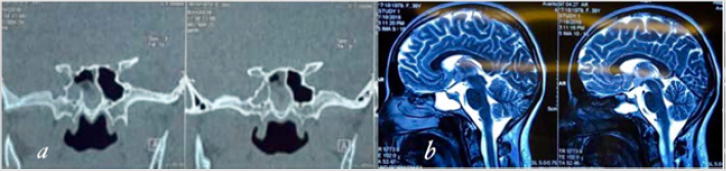

A 36-year-old female was admitted for three weeks of clear watery discharge from the right nostril, which was aggravated in prone position. The patient denied any recent trauma. A review of systems was negative except for headaches and nasal discharge. The nasal fluid tested positive for beta-2 transferrin, indicating that the fluid was CSF. Brain MRI revealed that the sphenoid sinus was filled with cerebrospinal fluid (CSF) and sagittal T2 weighted MRI revealed a fistula tract from prepontine cistern to sphenoid sinus (Figure 1). There was no evidence of benign intracranial hypertension. Computed tomography cisternography revealed that the contrast material passed from the prepontine cistern into the sphenoid sinus through this bone defect in the clivus (Figure 1).

Figure 1: (a) Coronal CT cisternography sphenoid sinus filled with CSF.

(b) Sagittal T2-weighted MRI of the brain showing cerebrospinal fluid (CSF) leak into the sphenoid sinus trough clival defect.